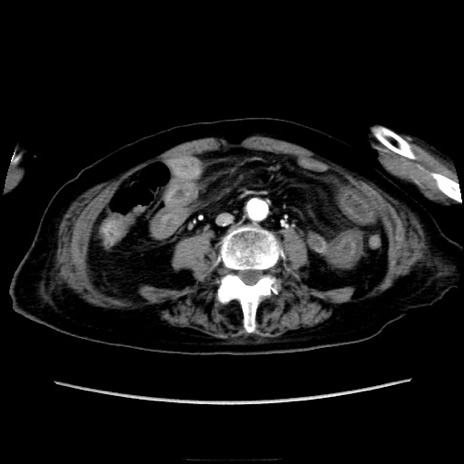

症例40(横断像)

【症例】90歳代女性

【主訴】腹痛・嘔吐

【現病歴】 食欲低下、嘔吐があり昨日他院受診。肺炎と診断され入院となる。入院後より腹部全体に圧痛あり。胃管留置され経過みていたが、症状持続するため、

当院転院となる。

【既往歴】胸椎圧迫骨折、胆石症

【身体所見】腹部:中央に激痛あり、圧痛あり、反跳痛不明

【データ】WBC 17100、CRP 18.82